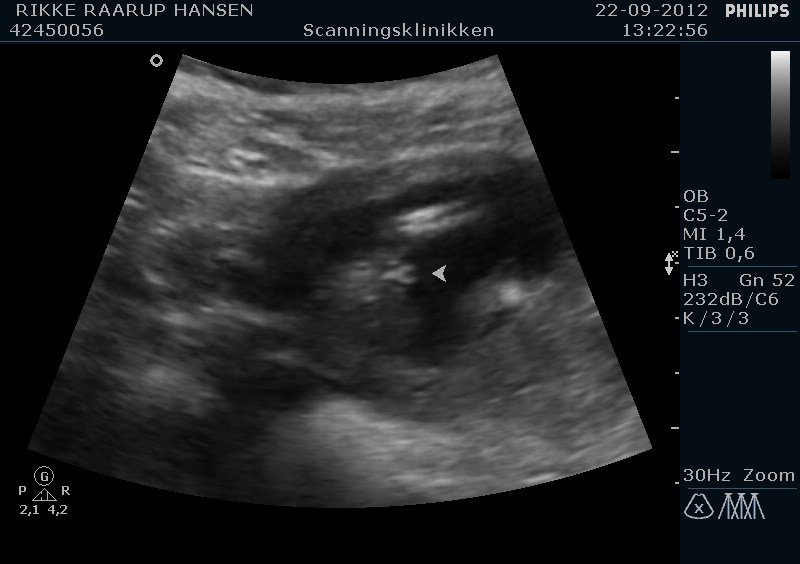

Stort tillykke med babydrengen

Her er et billede af vores fine babypiges undervogn

15+5 fik vi lavet kønsscanning.